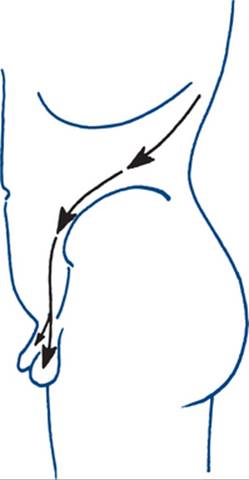

• It is bimanually palpable and ballottable — a hand from behind can displace the mass forwards where it is palpated by the hand in front. The sign is classic of a mobile retroperitoneal renal swelling but can be shared by any large flank swelling such as a very large liver or spleen (Fig 9.1).

Figure 9.1 Palpation of right kidney

The most common cause of loin pain is acute or chronic renal pain. Acute obstruction with dilatation of the urinary tract above the bladder causes acute renal pain (renal or ureteric ‘colic’) that has a wide distribution. Pain often radiates from the flank on the affected side to the anterior abdomen and groin and may extend into the penis or scrotum, or labia in females, or into the upper thigh (Fig 9.3). It is severe and prostrating in character and although described as ‘colic’ is usually continuously and unremittingly severe until relieved. Renal ‘colic’ is due to ureteric obstruction by stone, crystal, blood clot, necrotic papilla or infective debris, or back pressure due to a neuropathic bladder. Chronic renal pain gives a dull loin ache and can be due to a variety of renal and perirenal causes.

Figure 9.3 Renal ‘colic’

Typically, a continuous severe pain that radiates from the renal angle and flank to the abdomen, parallel to the inguinal ligament, to the base of the penis and into the scrotum.